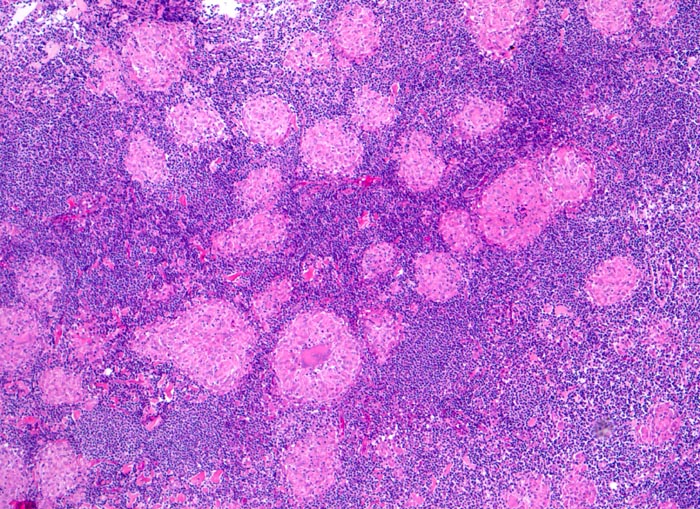

PathoPic ID 4013 - Lymphknotensarkoidose (Morbus Boeck)

Lymphknotensarkoidose (Morbus Boeck)

Systemerkrankung/Immunpathologie

Lymphknoten, inguinal

Lymphatische Gewebe, KM, Milz

Zahlreiche nicht verkäsende Granulome durchsetzen das Lymphknotenparenchym.

Vergrösserte inguinale Lymphknoten bei bekannter Sarkoidose mit Befall der Lungen.

Histologie

50